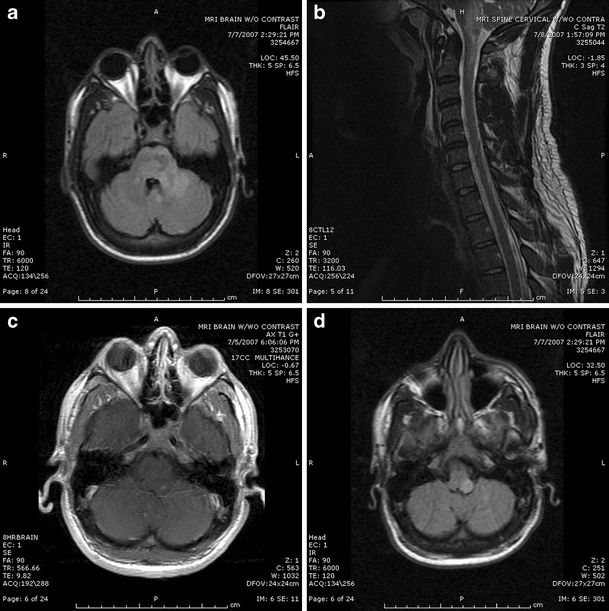

Moragas等报道的李斯特菌菱脑炎MRI异常达100%(幕下病变100%,幕上病变50%),而PNS所致菱脑炎患者MRI均正常。在病毒所致的菱脑炎中,70-75%的EV 71感染患者,50%的西尼罗河病毒感染患者,2/3合并疱疹感染患者(单纯疱疹病毒,Epstein-Barr病毒,巨细胞病毒,水痘-带状疱疹病毒和人类疱疹病毒6型)以及几乎100%的BD患者可见MRI异常信号。T2/FLAIR高信号病灶主要位于脑桥,延髓,上颈髓和小脑,而中脑累及少见。

(图1:李斯特菌菱脑炎患者;a:FLAIR可见左侧小脑中脚,小脑和脑桥高信号病灶;b:T2WI可见病灶延伸至上颈髓;c:T1增强可见左侧脑桥后外侧病灶强化;d:FLAIR上可见左侧延髓后外侧病灶)

(图2:李斯特菌菱脑炎患者;a,d:症状出现时的T2WI可见延髓和脑桥2处高信号非强化病灶;b,e:短期随访复查MRI可见病灶扩大伴新的幕下病变形成。c:DWI上部分病灶弥散受限;f:增强后可见环形强化;d:在疾病过程中,T2WI可见病灶继续进展伴广泛水肿,累及上颈髓区域;d,g:可见边界不清的幕下T2低信号区域的出现伴脑干肿胀和病灶边缘强化,符合出血性脓肿形成